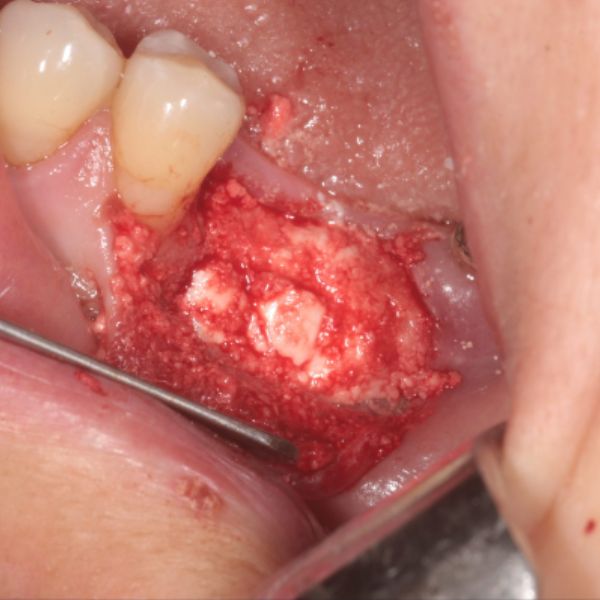

Dental Bone Graft - Upper Left Central